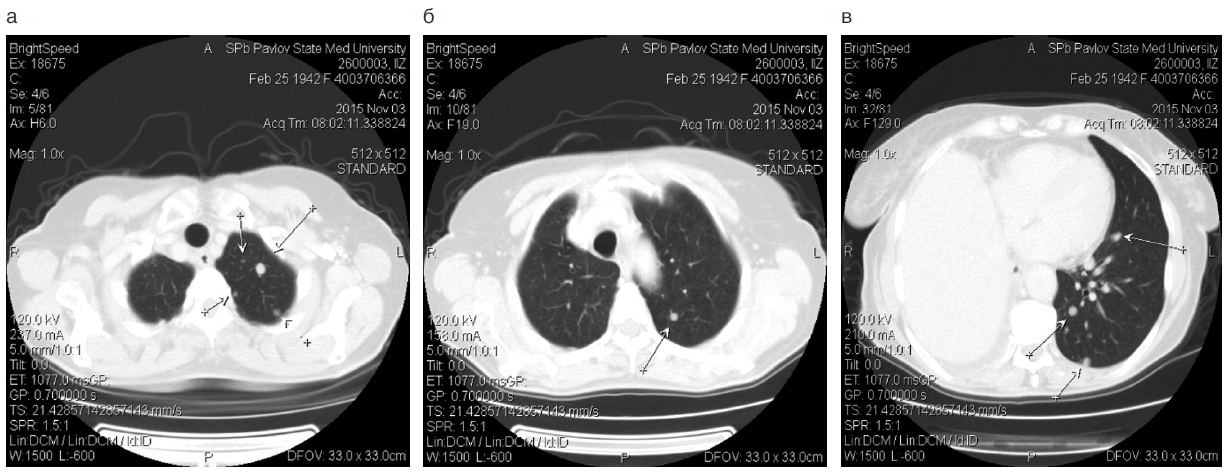

Через 3 мес после операции, в сентябре 2015 г., при контрольной КТ (рис. 1) выявлена прогрессия заболевания – появление метастазов в обоих легких, плеврит справа.

Рис. 1. КТ больной З., 73 года, ноябрь 2015 г.

Fig. 1. Computed tomography of patient Z., 73 years old, November 2015.